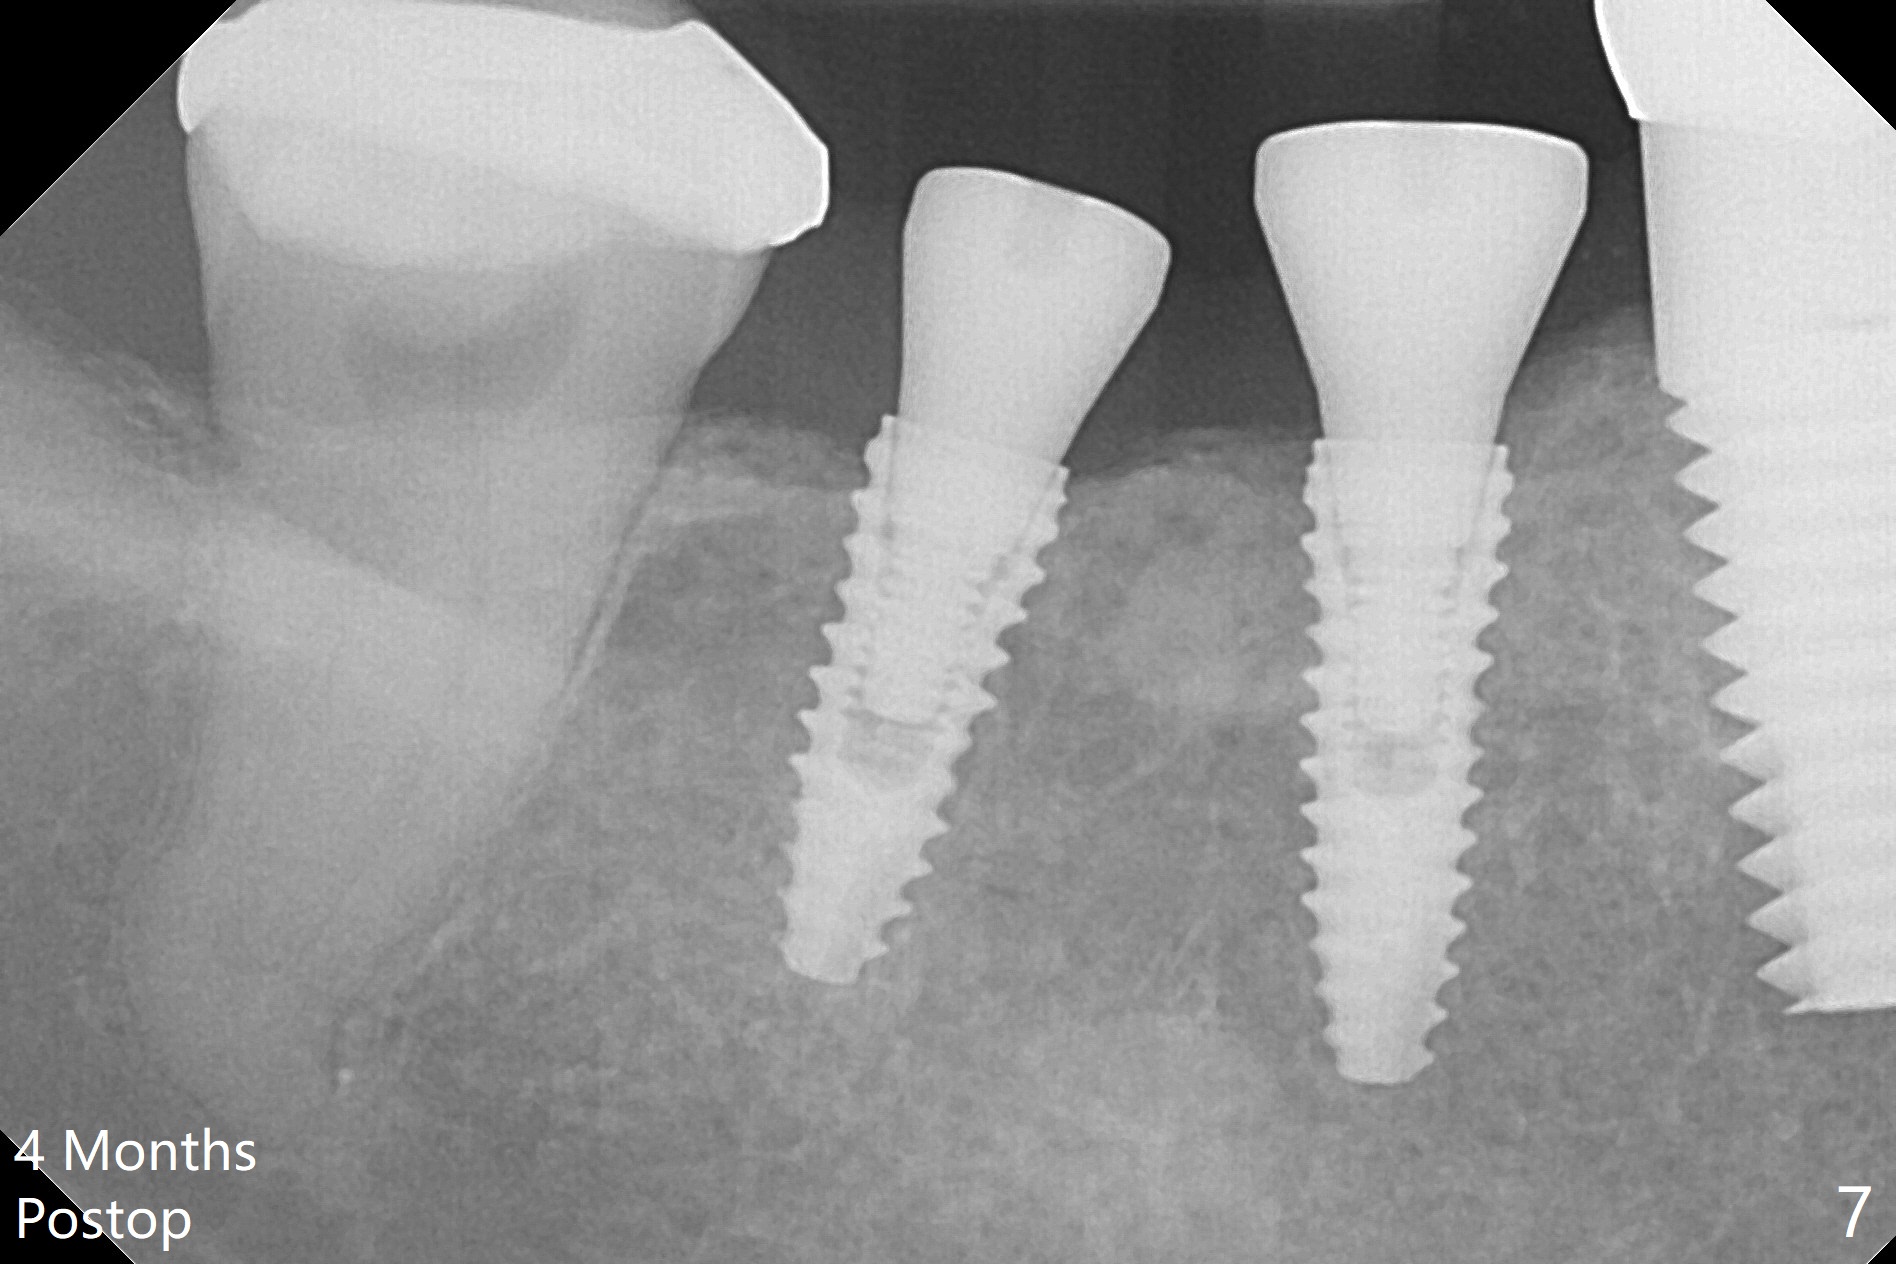

To reduce patient's expense, two implants are to be placed in narrow mesiodistal space (#30 and 31) free hand. Time is spent to determine where to place 4 mm tissue punch. When initial osteotomy is established (Fig.1), effort is paid to deciding whether the osteotomy is close to the Inferior Alveolar Canal (Fig.2 red dashed line). Since the gingiva is thin (Fig.4), implants switch to bone level ones (Fig.3,4). To have enough space between implants and the neighboring tooth, two of 3.5 mm implants are placed. Because of the limited vertical restoration height, the implants are chosen intraoperatively to be short and placed deep (Fig.3). Guided surgery planning can solve these pieces of dilemma beforehand.

In fact, detailed measurements after parallel pins indicate that the osteotomy at #30 should be moved distal (Fig.5 arrow), which is consistent with post placement measurements (Fig.6).

The patient with history of bruise after minor trauma returns next day. There is oozing from the site of #31. Hemostasis is achieved following periodontal dressing application and 2x2 gauze pressure. There is mild crestal bone resorption 4 months postop (Fig.7). Because of limited vertical space, the provisionals have dislodged by the time of cementation. It is difficult to seat the splinted crowns of #30 and 31. Bitewing is taken after cementation: the crowns have open margin (Fig.8). When a crown has high occlusion, X-ray should be taken prior to cementation.